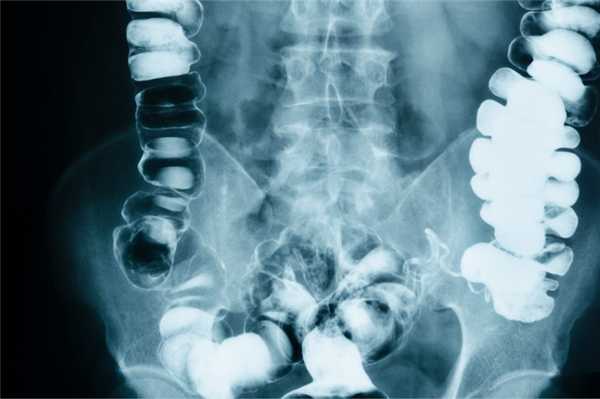

При обзорной рентгенографии брюшной полости определяются характерные кишечные арки (раздутая газом кишка с уровнями жидкости), чаши Клойбера (куполообразные просветления над горизонтальным уровнем жидкости), симптом перистости (наличие поперечной исчерченности кишки). Рентгеноконтрастное исследование ЖКТ применяется в затруднительных диагностических случаях. В зависимости от уровня кишечной непроходимости может использоваться рентгенография пассажа бария по кишечнику или ирригоскопия. Колоноскопия позволяет осмотреть дистальные отделы толстого кишечника, выявить причину обтурации кишки и в ряде случаев - разрешить явления острой кишечной непроходимости.

На сегодняшний день разработано множество методов диагностики непроходимости кишечника. Наиболее простыми и доступными из них являются различные рентгенологические методики. При подозрении на обтурационную кишечную непроходимость проводится обзорная рентгенография органов брюшной полости, на которой могут быть видны чаши Клойбера, горизонтальные уровни жидкости и арки воздуха. Эти рентгенологические признаки могут появиться в течение нескольких часов от начала заболевания. При необходимости может быть проведена прицельная рентгенография желудка и ДПК (при подозрении на инородное тело, желчные камни в начальных отделах кишки, аберрантную брыжеечную артерию), снимки в горизонтальной и латеропозиции, на правом или левом боку.

Если явных признаков непроходимости выявлено не будет, рекомендуется провести рентгенологическое исследование с использованием контраста (рентгенографию пассажа бария по тонкому кишечнику, ирригографию). Контрастирование обычно позволяет точно установить локализацию и уровень непроходимости кишечника.